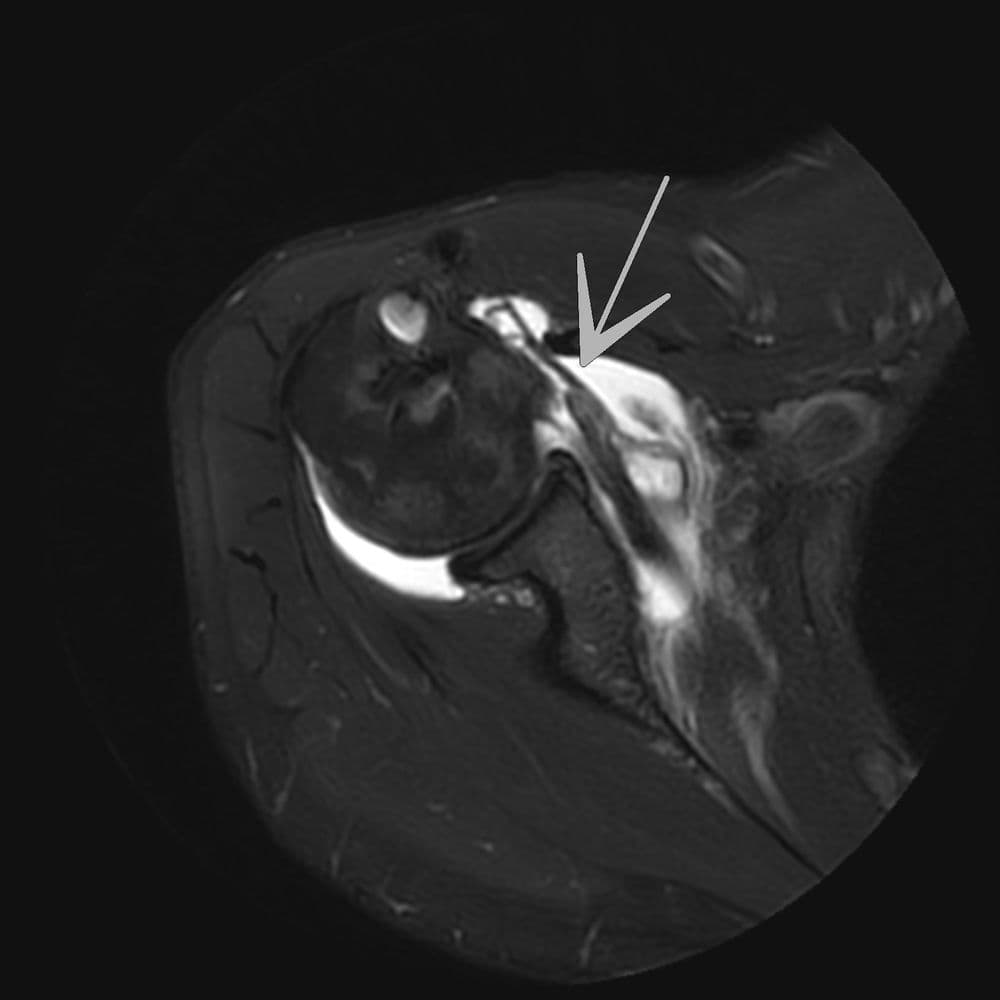

Antécédent de ténodèse du long biceps il y a 10 ans. Douleurs post traumatiques. Réévaluation lésionnelle

MRIRX

Lésion traumatique brutale de la portion intra articulaire du biceps de l'épaule droite

MRI